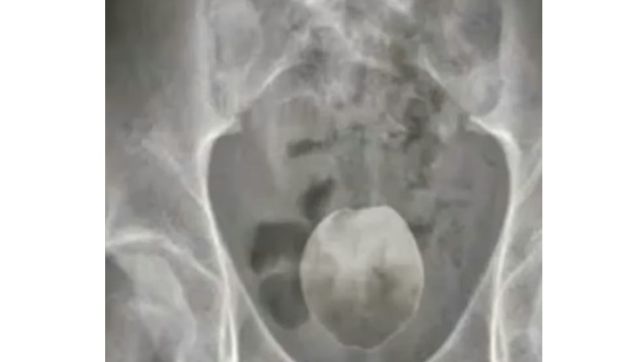

Um homem de aproximadamente 50 anos deu entrada no Pronto Atendimento Municipal da cidade após relatar fortes dores abdominais provocadas pela introdução de um coco verde no ânus.

De acordo com informações de sites locais, o objeto teria o tamanho aproximado de uma mão e causou obstrução intestinal grave, o que motivou a transferência do paciente ao Hospital São Lucas, onde foi submetido a uma cirurgia para remoção do corpo estranho.

O procedimento cirúrgico foi bem-sucedido e o homem encontra-se em estado clínico estável, em observação hospitalar. A identidade dele está sendo mantida em sigilo.